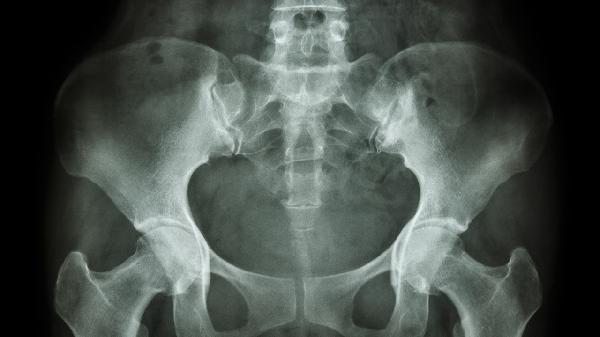

恥骨疼痛嚴重可能與妊娠相關韌帶松弛、恥骨聯(lián)合分離、外傷、泌尿系統(tǒng)感染、骨質疏松等因素有關,可通過休息制動、物理治療、藥物鎮(zhèn)痛、手術治療等方式緩解。

分娩過程中可能發(fā)生恥骨聯(lián)合過度分離,表現(xiàn)為局部壓痛、下肢活動受限,嚴重時出現(xiàn)步態(tài)異常。該情況需通過骨盆X線或超聲確診,輕度分離可通過臥床休息、骨盆束縛帶固定恢復,疼痛明顯者可短期使用洛索洛芬鈉片消炎鎮(zhèn)痛。若分離超過10毫米且保守治療無效,可能需要手術復位固定。